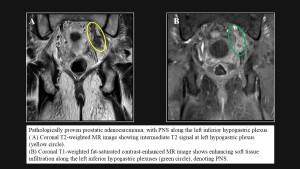

MRI features of PNS :

- Nerve enlargement on T1-weighted images.

- Abnormal signal on T2-weighted images.

- Perineural enhancement on contrast-enhanced sequences.

Prostatic cancer

In prostatic cancer, perineural spread commonly involves the neurovascular bundle (NVB), which can be readily visualized on MRI and is considered a component of extraprostatic extension. Accurate detection of NVB involvement is critical for management, influencing decisions regarding surgery and the need for adjuvant therapies. On MRI, the NVB is located along the dorsolateral prostate and anterolateral rectum. Normally, it appears as low-signal-intensity foci within a triangular or round area of hyperintense fat at the prostate base and mid-gland on T1- and T2-weighted images. Involvement is suggested by asymmetrically enlarged nerves compared with the contralateral side, indicating tumor infiltration along the nerve sheaths.